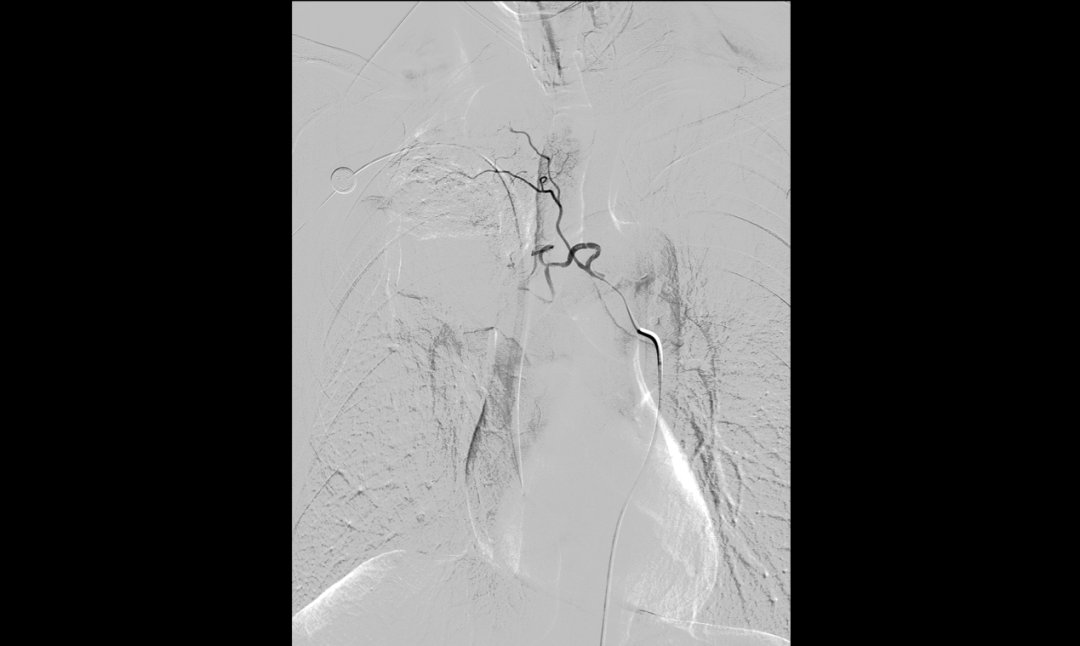

▲BACE术后肿瘤血流速度明显减慢

面对复杂的病情,呼吸与危重症医学科学科带头人、省医派驻专家罗少华指出,患者基线肿瘤分期属IIIB期,常规的免疫+化疗方案疗效不佳,存在肿瘤耐药情况,可尝试载药微球支气管动脉化疗栓塞术,以期缩小病灶,为手术创造机会,呼吸介入团队经过缜密的术前讨论和评估,认为患者有BACE适应证。征得患者及家属充分知情同意后,呼吸介入团队成功为患者实施了BACE手术,术后造影显示肿瘤区造影剂滞留,血流速度明显减慢,封堵效果满意,标志着手术取得圆满成功。